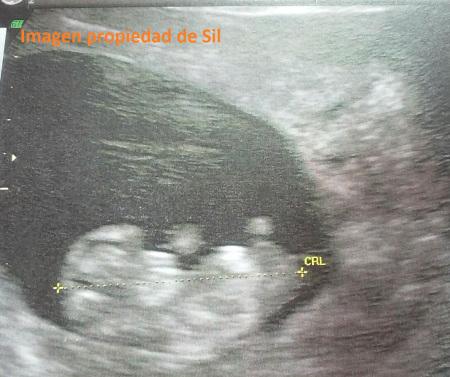

Sería en la segunda o tercera ecografía, Gini hacía una al mes, más o menos, cuando sobresaltada manifestó: uy, qué bebé tan grande! Extrañada le pregunté mirando la pantalla: ¿estás segura? Si apenas mide unos centímetros! y ella respondió perspicaz: “mira qué pies! y qué manos! es enorme!!”

Mini Thor ya era grande con pocos centímetros de vida.

Poco después, con la siguiente o sucesiva visita, la sorpresa fue aun más mayúscula cuando Gini, buscando el sexo del bebé descubrió atónita que lo que ella pensaba que era una pierna… era la señal inequívoca de que Mini Thor iba a ser un varón de pelo en pecho. Mi marido me confesó en privado, aunque ahora yo lo haga manifiestamente público, que apenas vio nunca NADA en ninguna ecografía (jaja, pobre) y eso que nos las hacía en 3D y 4D!! Y a pesar de no terminarse de creer tanta predicción, se le notaba que estaba contento. Como ya he comentado en alguno de los primeros capítulos, mi tripa era inmensa y mi movilidad reducida. Las patadas de Mini Thor eran de futbolista profesional en la tanda de penaltis, y en el parto también he comentado que se quedó atascado por grande.